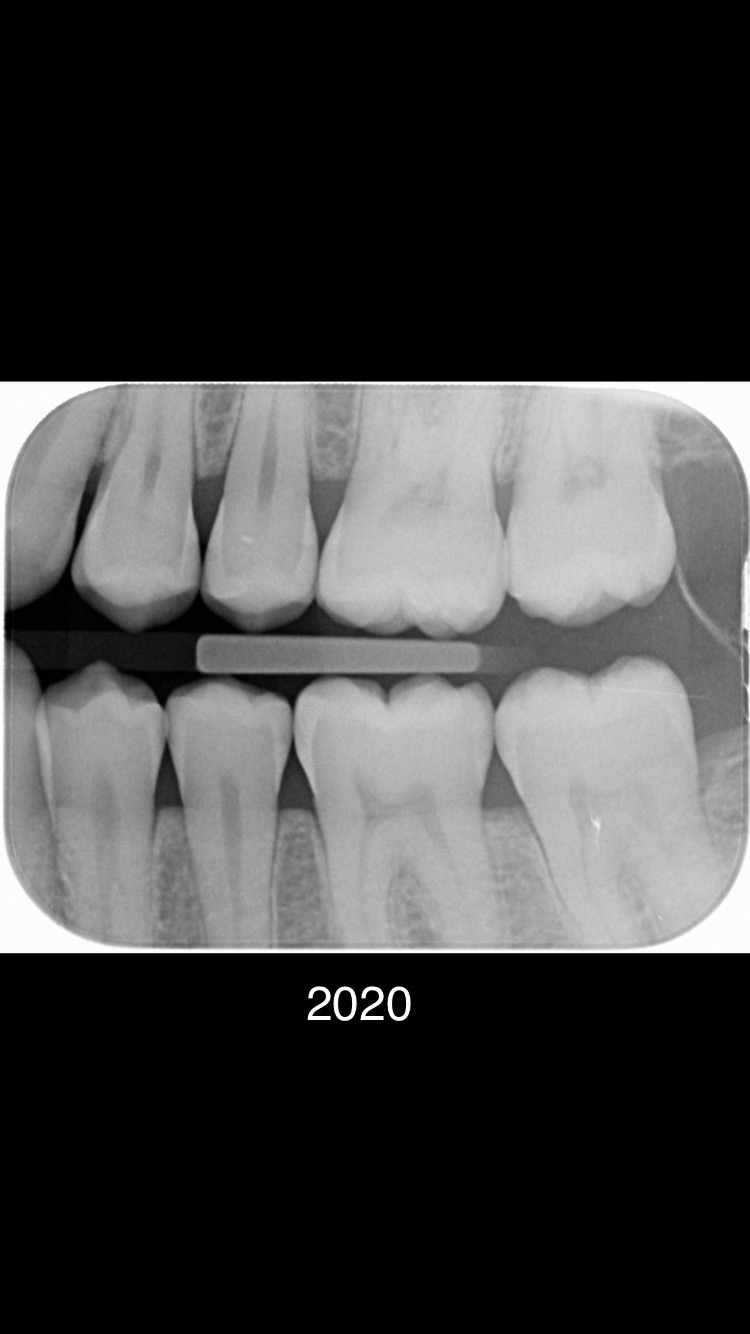

Er zijn meerdere beginnende plekjes maar die zijn nog niet door het glazuur dus hoeven nog niet aangepakt te worden. De vier in de linker boven en onderkaak gevonden "gaatjes" zou ik ook aanpakken. 25.26.35,36.......24 kan ik niet goed beoordelen dus twijfel.16 zou ik nog niet doen. In 2021 waren er links enige die net wel of net niet door het glazuur zijn.. dus ik kan begrijpen dat uw tandarts dat in de gaten heeft gehouden, gemonitord. Maar wat heeft u gedaan tussen 2020/2021 en 2023.. Gebruikt u wel ragers elke dag???>of andere reiniging hulpmiddelen voor tussen de tanden en kiezen. Let op uw voeding/drank gebruik... beperk het aantal invloed momenten op uw gebit tot 6. etc etc. dit gaat fout. Op de status praesens v uw gebit zie ik maar 5 aantekeningen niet 7. Maar ik ben niet goed in rekenen.

Helaas alle praktijken moeten verdienen... Het is een onderneming geen charitatieve instelling. Alle prijzen worden voor ons door NZA bepaald hebben wij niets over te zeggen. Lees mijn advies hierboven wat gaatjes betreft. Niet elke dag tussen alle tanden en kiezen een rager gebruiken vind ik zeer onverstandig. Zie alle defecten...zijn allemaal tussen de kiezen waar een tandenborstel niet maar een rager wel kan komen. Wanneer bent u voor het laatst bij de tandarts geweest??. Blijkbaar gaat er iets fout. Houdt bij zoals ik heb aangegeven en bespreek dat met de mondhygiënist. Laat ook daadwerkelijk zien hoe u reinigt er gaat iets fout. Dat v niet elke dag een rager gebruiken is er een. Als al beginnende "gaatjes" zijn niet elke 6 mnd naar de tandarts gaan is nr 2. Foto v 2021 was niet alarmerend maar toen is iets fout gegaan. Dus in twee jaar tijd.

Je gaat toch niet zelf de gaatjes vullen ??.Heeft u mijn verbaasde vraag hierboven gelezen of u een rager gebruikt. Ik ben blij als mijn cliënten 2xdgs een rager gebruiken, minimaal 1xpd.n Het gaat om de meest recente foto. De oude foto's geven een beeld v progressie v defecten.